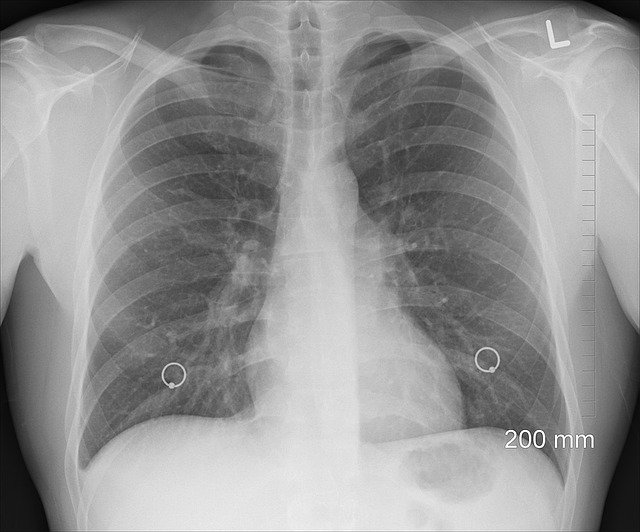

3. 갈비뼈

외상으로 인해서 갈비뼈가 금이 생긴 경우 가슴통증이 생깁니다. 운동을 하다가 충격이 가거나 근육통으로 인해서도 통증이 생기기 도하지만 근육에서 통증이 생기는 것이기 때문에 힘을 주는 것으로 간단하게 알아볼 수 있습니다. 골절이나 금이 간경 우 통증 부위의 뼈를 만져보고 통증이 느껴지는 경우 X-ray를 찍어보는 것이 좋습니다.